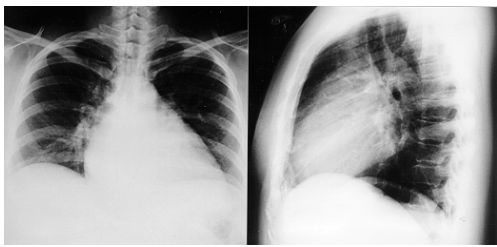

3. 其胸部X光如附圖1. 右心房擴大2. 右心室擴大3. 左心房擴大4. 左心室擴大5. 縱膈腔腫瘤 (A) 1, 3 (B) 1, 3, 5 (C) 2, 4 (D) 2, 3 (E) 2, 4, 5